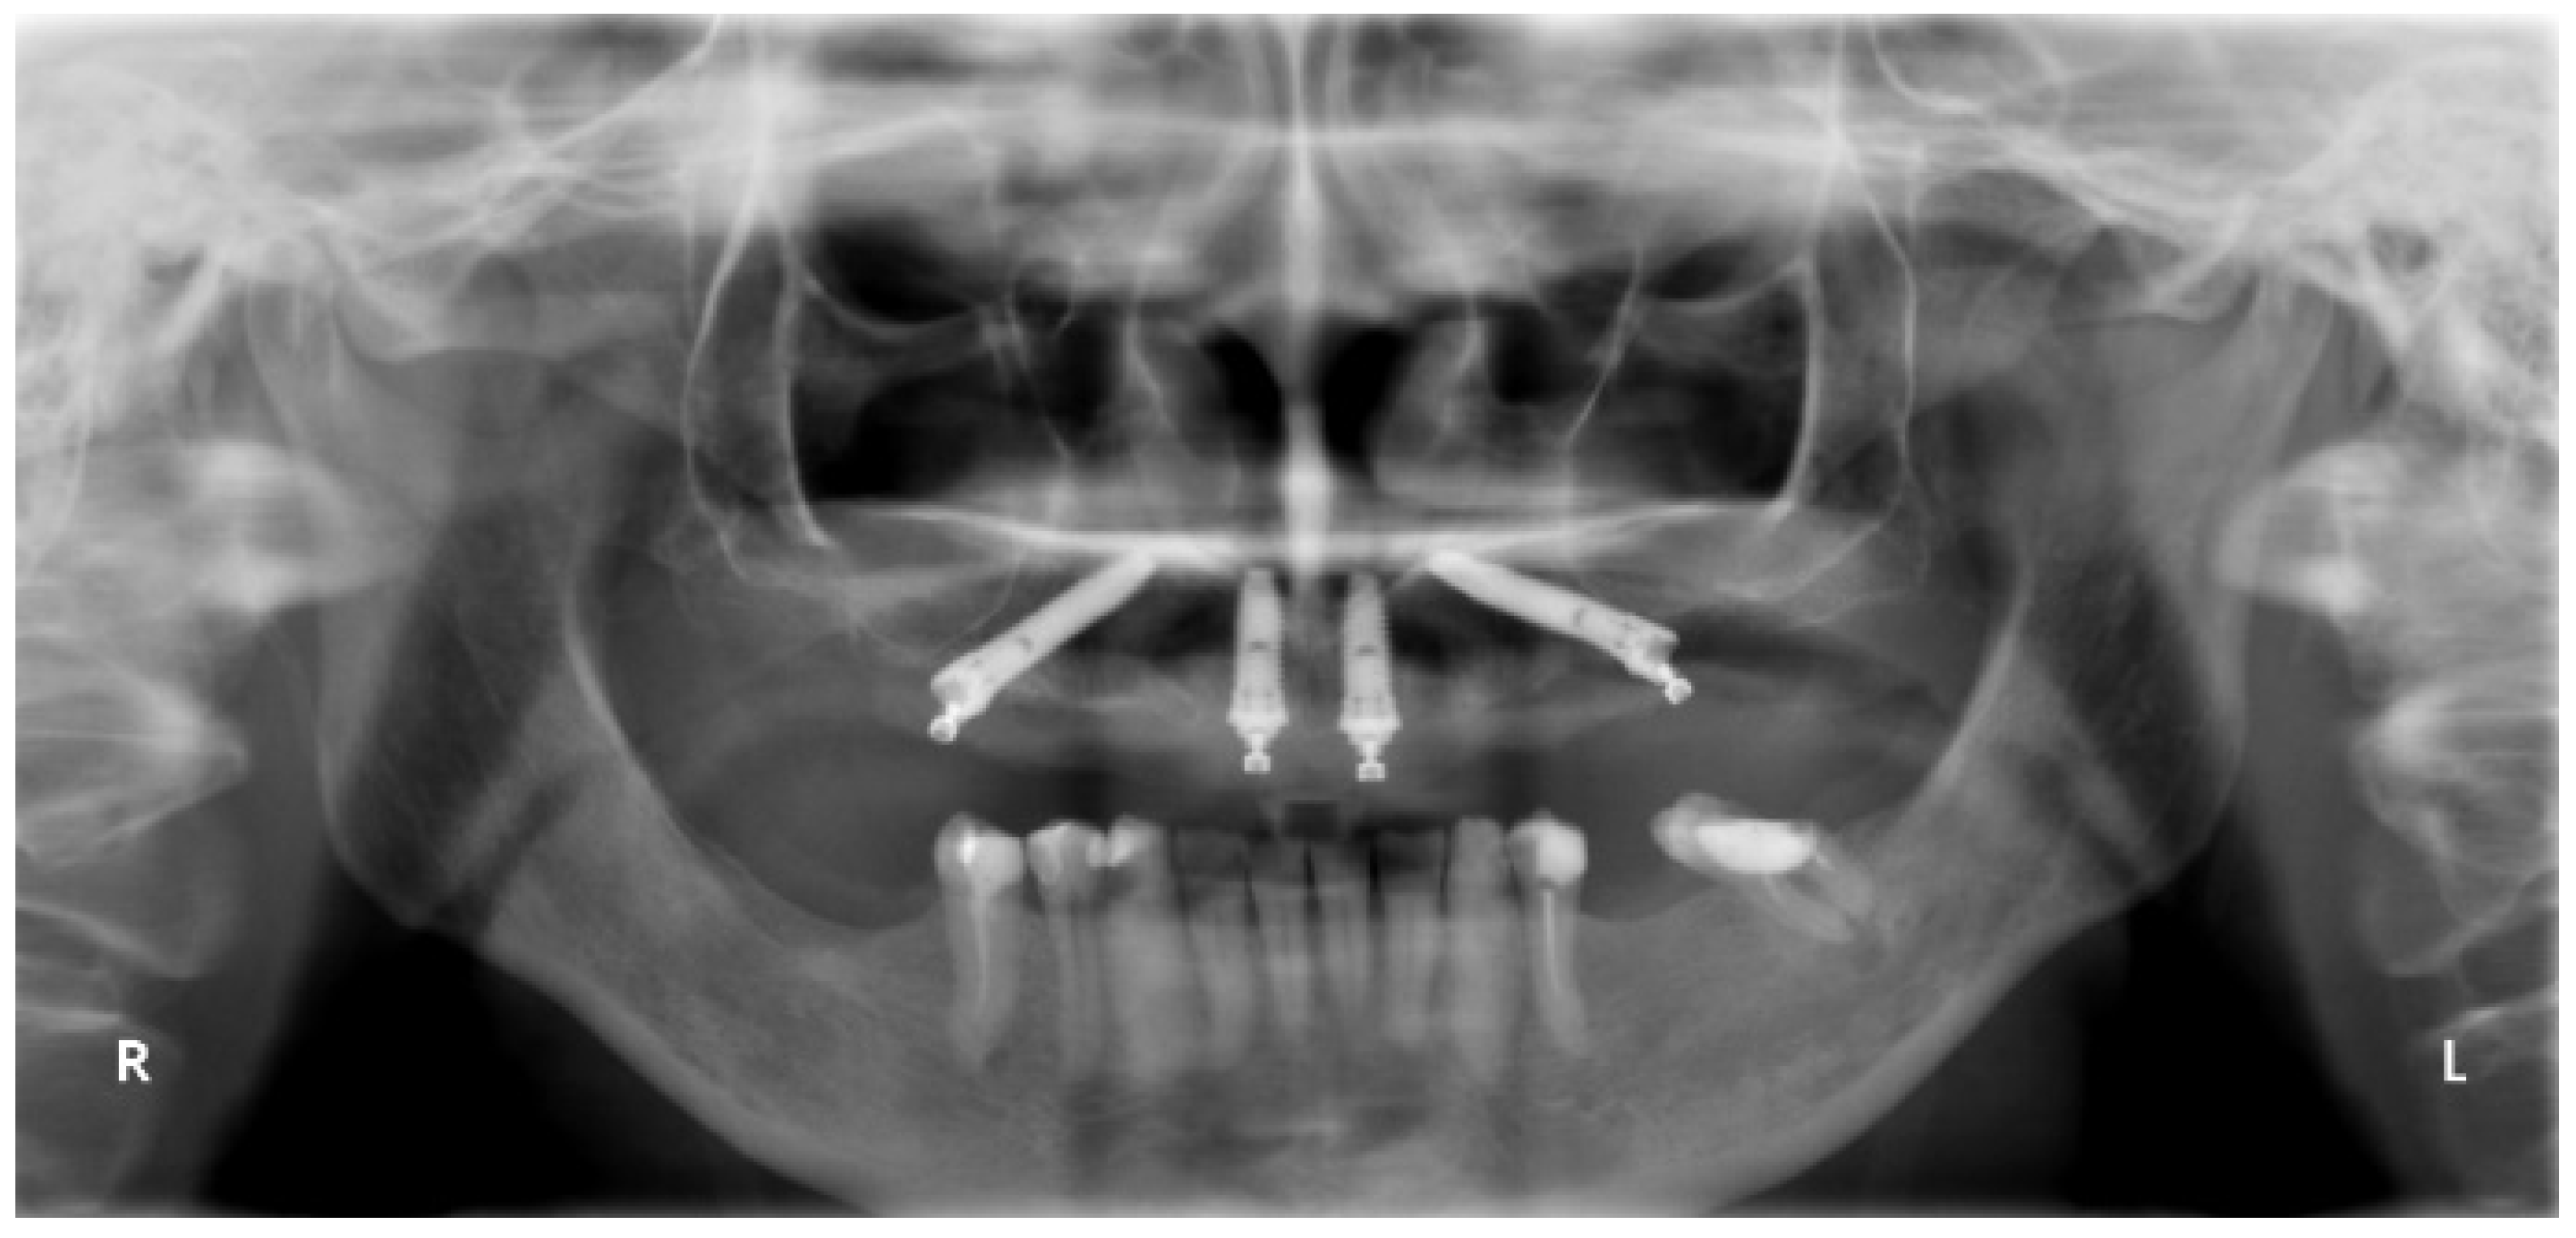

All patients were evaluated clinically up to 7 years and radiographically at 1-, 3- and 5 years. The pretreatment orthopantomography is presented in Figure 2.

Figure 2. Pretreatment orthopantomography.